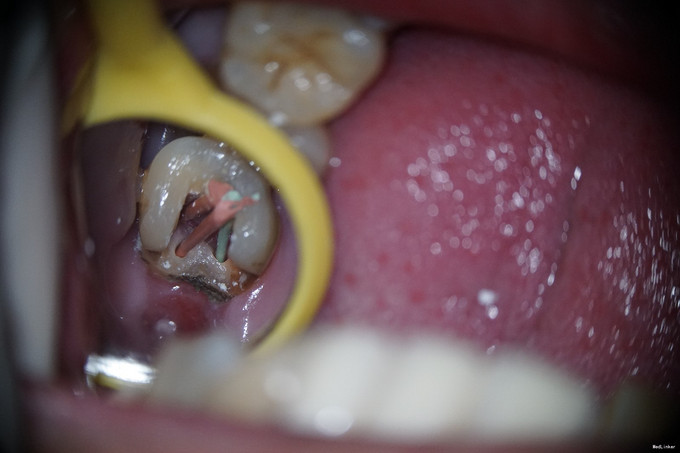

检查:27牙远中邻he面见大面积龋坏组织,质软,探及穿髓孔,探(-),叩(+-),根尖区扪(+-);松动I度;颊侧牙槽粘膜及牙龈未见明显窦道。28牙于我科就诊时已拔除。 全景片示27牙远中低密度影,累及髓腔;无清晰根管影像;牙槽嵴高度正常;牙周膜间隙正常;根尖周组织未见低密度影。

诊断:27牙慢性牙髓炎 治疗方案: 1、27牙根管治疗+充填修复+冠修复 2、27牙显微根尖外科手术 3、27牙干髓术 4、46牙择期治疗 经与患者详细介绍每种治疗方案的治疗经过、费用及预后,患者选择方案1。 治疗经过: 初诊:因患者咽反射强,无法上橡皮障。27牙涡轮机去龋,未去净龋坏时见穿髓孔,但因髓腔钙化及解剖牙冠长,不能探及明显髓腔结构;ET20清理髓腔内钙化,探及3根管口。其中近颊根根管口探痛明显,封“三聚甲醛”;CAVITON暂封。 首次复诊:27牙去净暂封,根测仪测定根管长度,近颊根19mm,远颊根19mm,腭根20mm;机用镍钛器械Protaper清扩至#2506锥度,腭根清扩至#3504锥度,示尖到位;超声荡洗,次氯酸钠冲洗,纸尖吸干,根管内封氢氧化钙,髓腔置干棉球,CAVITON暂封。 二次复诊:27牙去暂封,去棉球,超声荡洗根管,次氯酸钠冲洗,再次测量根管长度,纸尖吸干,AH糊剂+大锥度牙胶尖封闭根尖段,热牙胶封闭根中上段,拍片示根充到位;腭根预备纤维桩道,冲洗,干燥,粘接#13纤维桩;涂布粘接剂,流体树脂垫底,3M纳米树脂充填修复,调he,抛光。

1、从全景片中可见,该牙龋坏已与髓腔相通,髓腔较为明显。但开髓时发现,髓腔内几乎均钙化,髓腔空间及其狭小。且该牙解剖牙冠长,且为上颌最后颗磨牙,若对牙体解剖没有足够地掌握,没有充足的经验,非常容易开髓开偏或找不到根管口,或有遗漏根管,因为近颊根根管口被钙化的牙体组织完全覆盖。此种情况下,若使用涡轮机企图去除牙体组织后寻找根管口非常困难,若在显微镜下使用超声则为最佳选择。 2、该牙虽然冠的上部牙体组织无去坏,但仍然去除掉了。虽然对牙齿的创伤较大,但若不去除这些无机釉,一来可能龋坏无法去除干净,二来抗力形不足,容易折断。 3、该牙髓腔内牙髓完全坏死,但各个根管内均有较好牙髓活力。说明牙髓的坏死是一个渐进的过程,即便是髓腔及根管开始钙化,牙髓也可有活力。